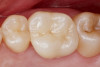

Figure 1 through Figure 14 illustrate steps involved in the fabrication of zirconia restorations using CEREC. Figure 15 through Figure 21 show preparations and postoperative results in two case examples of patients who received zirconia indirect restorations.